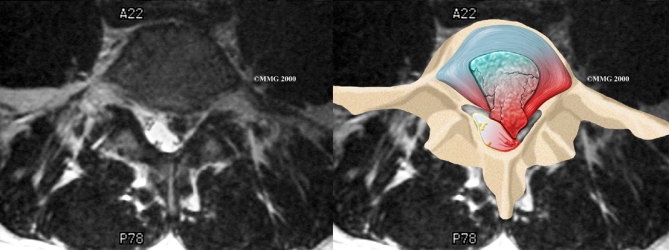

When more information is needed, your doctor may order magnetic resonance imaging (MRI). The MRI machine uses magnetic waves rather than X-rays to show the soft tissues of the body. It gives a clear picture of the discs and whether a herniation is present. Like the CT scan, this machine creates pictures that look like slices of the area your doctor is interested in. The test does not require special dye or a needle.

Magnetic Resonance Imaging (MRI)